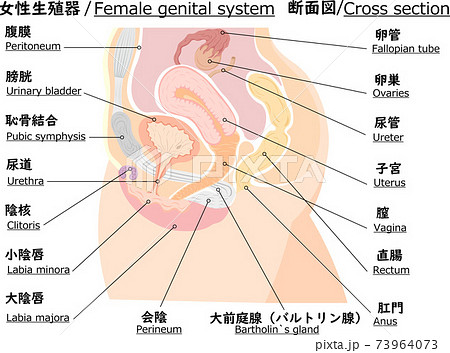

女性器の断面図 Listen さくやの囁き

子宮横からの断面図 名称付き メディカルイラスト図鑑 無料の医療 美容素材集

骨盤 女性 解剖学 切断断面 卵巣 卵管 子宮 膀胱 膀胱 尿路 クリトリス 尿道 尿道括約筋 膣 外陰結腸 直腸括約筋が示される のイラスト素材